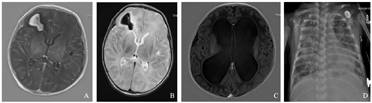

例1 患儿,男,14 d,因"发热4 d,抽搐半天"由当地医院转入我院。入院后血常规示白细胞计数6.22×109/L,C-反应蛋白(C-reactive protein,CRP) 3.66 mg/L。脑脊液常规:细胞数23×106/L,多个核细胞10%,单个核细胞90%;脑脊液生化:蛋白2 909 mg/L,糖2.43 mmol/L,氯化物112 mmol/L;脑脊液培养、血培养和痰培养均未见致病菌生长。头颅MRI示:右额叶出血(亚急性期),双侧侧脑室旁微出血灶(图1A、B)。脑电图示异常脑电图,低电压活动。入院后先后给予哌拉西林他唑巴坦、美罗培南抗感染及对症治疗,患儿病情进行性加重出现持续抽搐、昏迷,复查血常规示白细胞计数12.52×109/L,CRP 0.43 mg/L。脑脊液常规:细胞数575×106/L,多个核细胞15%,单个核细胞85%;脑脊液生化:蛋白15 957 mg/L,糖2.12 mmol/L,氯化物114 mmol/L,脑脊液培养无致病菌生长;脑脊液mNGS结果:人单纯疱疹病毒2型(表1),完善血单纯疱疹病毒IgM及IgG阳性,风疹病毒IgM阳性,弓形虫IgM阳性。确诊单纯疱疹病毒脑炎,予阿糖胞苷抗病毒治疗,入院第10天出现呼吸衰竭予机械通气,家属考虑预后欠佳于入院第12天要求终止治疗。

A、B:例1患儿头颅磁共振成像示右额叶出血(亚急性期),双侧侧脑室旁微出血灶,双侧小脑半球异常信号,双侧基底节区异常信号;C:例2患儿头颅磁共振成像示双侧脑室扩张,重度脑积水;D:例4患儿X线胸片示两肺野透过度减低,可见多发斑片致密影。

例2 患儿,女,5 h,因"胎龄29+1周,生后呼吸困难5 h"入院。系试管婴儿双胎小婴儿,第2胎第2产,出生体重1 350 g,第1胎孕7个月早产生后夭折。入院后先后给予机械通气、持续气道正压无创呼吸支持、肺表面活性物质应用、抗感染、静脉营养等对症支持治疗。入院第19天无创辅助通气下出现呼吸暂停,反应差,肤色发花,经皮血氧饱和度不稳定。查血常规:白细胞计数33.26×109/L,中性粒细胞百分比77.5%,血红蛋白120 g/L,血小板计数435×109/L,CRP 12.67 mg/L。脑脊液常规示:细胞数1 244×106/L,多个核细胞95%,单个核细胞5%;脑脊液生化:蛋白2 785.6 mg/L,糖0.05 mmol/L,氯化物118 mmol/L;脑脊液培养:未见致病菌生长。诊断为新生儿化脓性脑膜炎,先后予美罗培南联合万古霉素、氟康唑联合头孢曲松及万古霉素、哌拉西林他唑巴坦联合头孢曲松及氟康唑治疗2月余,患儿反应仍差,脑脊液细胞数始终未恢复正常。患儿先后5次血培养,14次脑脊液培养,1次痰培养均无致病菌生长,入院73 d脑脊液mNGS结果检测到微小脲原体(表1),查头颅MRI示双侧脑室明显扩张,脑积水(图1C)。更改治疗方案为红霉素抗感染治疗1周后病情好转,脑脊液细胞数明显下降,3周后完全恢复正常,治愈出院,后入住小儿神经外科行脑室分流术,随访至1岁,患儿发育良好。

例4 患儿男,26 d,因"咳嗽7 d,发热3 d,呼吸困难15 h"由当地医院转入我院。第1胎第1产,胎龄34+1周,出生体重2 150 g,未接种卡介苗及乙肝疫苗。X线胸片示两肺炎症并间质性改变(图1D),血CRP 92.3~143.3 mg/L,入院后2次血培养、脑脊液培养未见异常,2次痰涂片见少量革兰阴性杆菌生长,未见致病菌生长,抗酸染色阴性,骨髓检查无异常。诊断为新生儿败血症及重症肺炎,先后给予美罗培南、万古霉素、利奈唑胺、氟康唑、卡泊芬净抗感染及机械通气等治疗,病情持续进展,科室疑难病例讨论认为非典型致病菌感染可能性大。入院第8天血和肺泡灌洗液mNGS标本均检测到结核杆菌复合群(表1),再次复查痰涂片示抗酸染色阳性,血结核抗体TB-(F6抗原)抗体IgG弱阳性,结核分支杆菌复合群基因阳性。之后获悉其母亲在患儿发病前已经出现低热、咳嗽,患儿确诊后其母亲在结核病专科医院亦确诊肺结核并给予抗结核治疗。该患儿确诊后转入专科医院给予病因治疗,治愈出院。